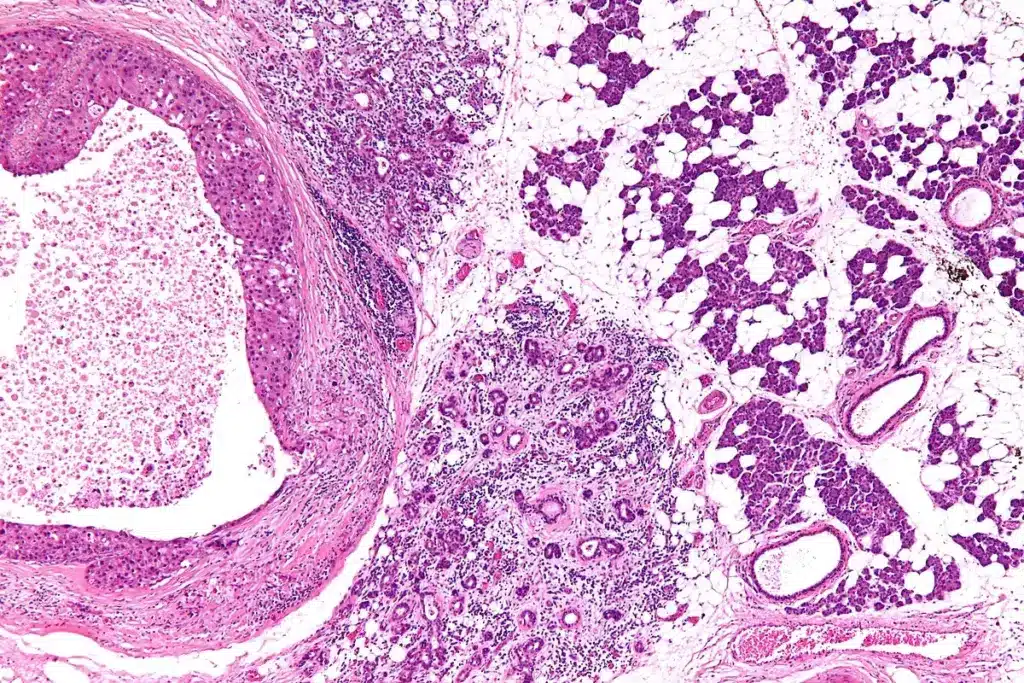

Cellular Composition of Salivary Glands

The glands have different cells, like acinar and ductal cells. Acinar cells make saliva, and ductal cells form the ducts that carry it to the mouth.

The type of cells in each gland affects the saliva it produces. For example, the parotid gland has more serous acini, making a saliva rich in enzymes.

Ductal System and Its Organization

The glands are divided into lobes, then lobules, and acini. The ductal system is key in changing the saliva as it moves through the ducts. This adjustment helps the saliva reach the mouth ready for use.

The glands have glandular acini, which are key for making saliva. These acini can be serous, mucinous, or mixed. Serous acini make a watery liquid with enzymes, while mucinous acini make a thicker, mucin-rich liquid for lubrication.

The process of making saliva involves acinar cells and myoepithelial cells working together. Acinar cells make the initial saliva, and myoepithelial cells help push it out. As the saliva moves through ducts, it gets modified. This results in the final saliva we get in our mouths.